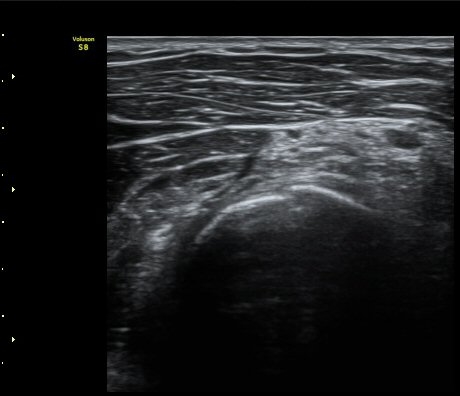

ÆÈ²ÞÄ¡ ¿ÜÃø¿¡¼­ ½ÃÇàÇÑ ¿ä°ñµÎ Á¾´Ü¸é°Ë»ç¿¡¼­ ¿ä°ñµÎ¿Í ¿ä°ñ °æ°èºÎ°¡ ¿¹°¢À¸·Î ÀÌÇàµÇ°í

°æ°èºÎ¿¡ ¼Ò·®ÀÇ ¼ö¾×Àú·ù°¡ °üÂûµÊ(±×¸² 2)